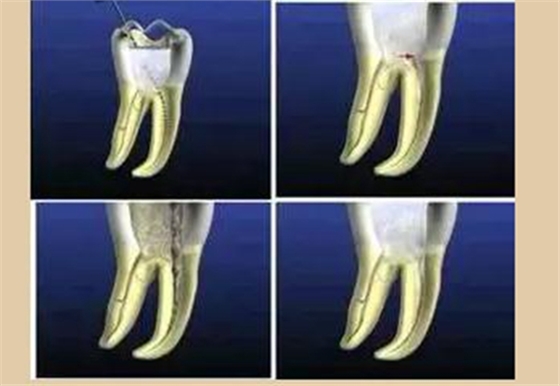

根管治療術(shù)是醫(yī)生用根管治療專用器械通過(guò)徹底去除感染的牙髓以及感染的牙本質(zhì)和毒性分解產(chǎn)物,經(jīng)過(guò)根管沖洗、消毒和嚴(yán)密填塞根管,隔絕細(xì)菌進(jìn)入根管再感染,防止根尖周病變的發(fā)生或促進(jìn)根尖周病的愈合。

根管預(yù)備是通過(guò)機(jī)械方式配合化學(xué)藥物去除、清理根管里面的污染物,使根管成為一定形態(tài),利于沖洗和充填。

便宜形態(tài)是自切端或咬頜面朝向根尖的直線開(kāi)擴(kuò)尖錐形態(tài),減少污染物推出根尖孔,方便沖洗、根管充填和側(cè)壁施壓。

保持形態(tài)是根尖狹窄部?jī)?nèi) 1 — 2mm 的一段距離,由擴(kuò)大器回轉(zhuǎn)切割而不貼根管壁提拉切割制成,是擴(kuò)大器的原始形態(tài)(近似平行)。在測(cè)試主牙膠尖時(shí)給測(cè)試者有一個(gè)牽引抵抗 (tugback) 的感覺(jué)。

抵抗形態(tài)是根管預(yù)備的根尖形態(tài),它是由擴(kuò)大器或根管銼尖端 75 度角自然切割而成。其目的是防止根管充填材超出根尖孔,并且使根尖封閉更加嚴(yán)密。